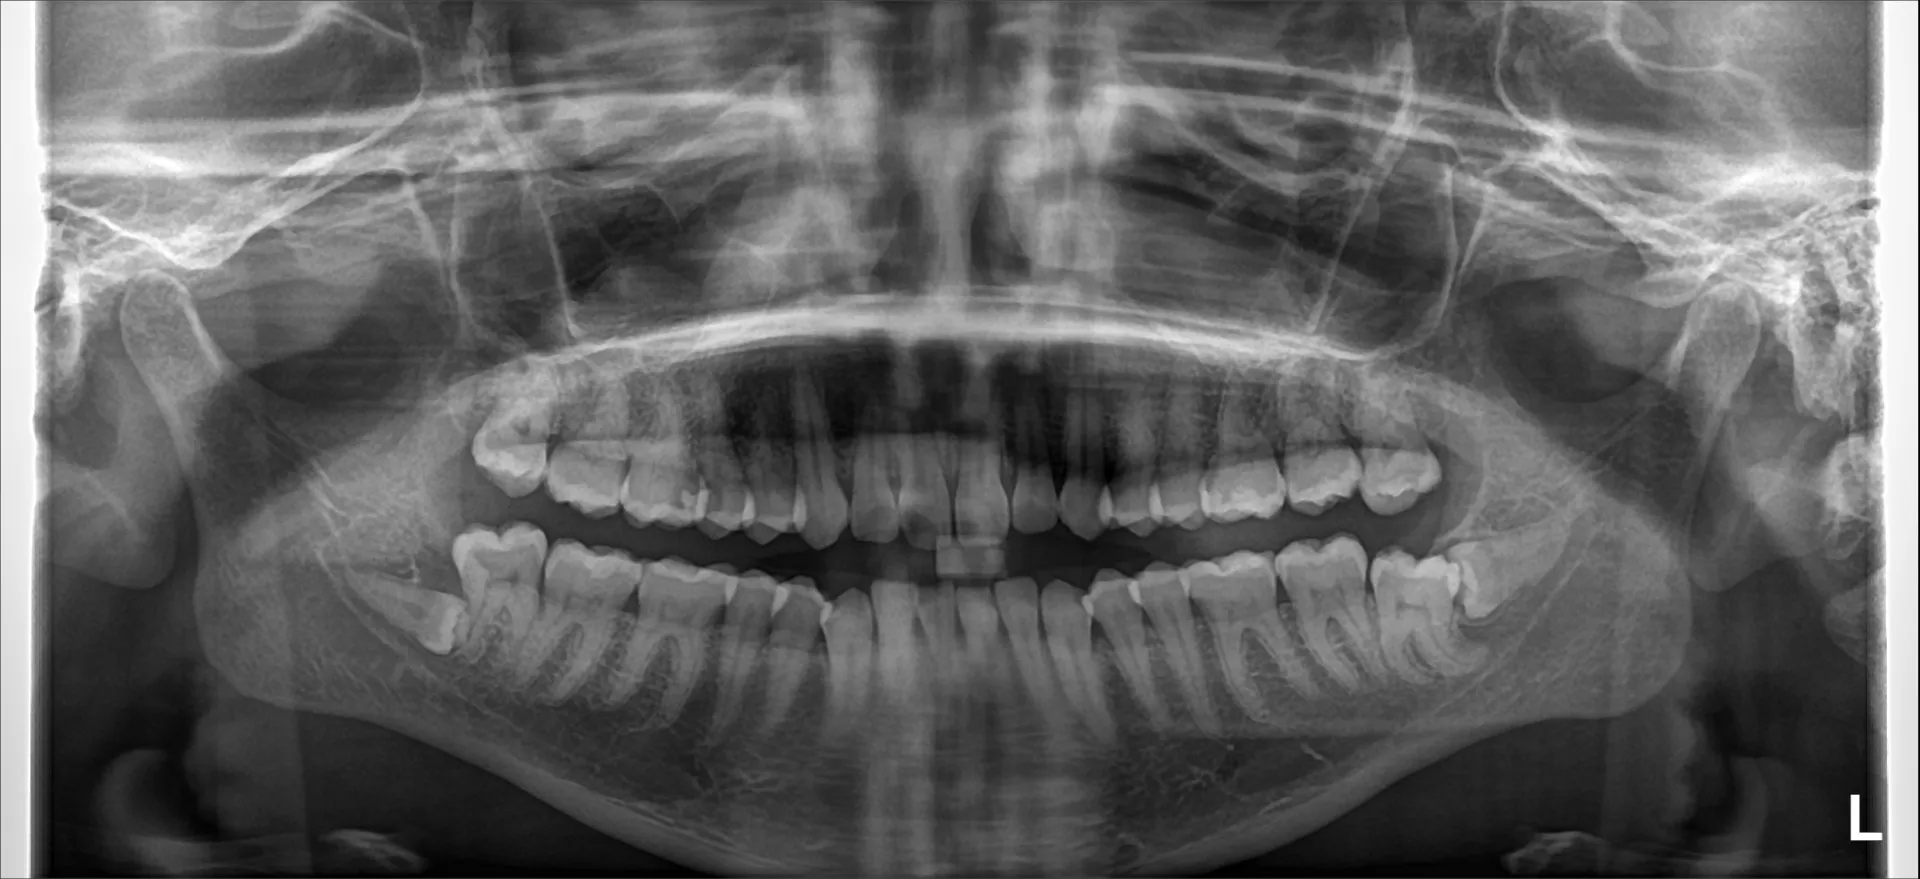

パノラマレントゲン写真

親知らず(下顎智歯)の抜歯難易度を評価する際に用いられる代表的な分類のひとつが Winter分類(Winter’s Classification) です!

これは 親知らず(下顎第三大臼歯)が第二大臼歯に対してどのような方向で埋伏しているか を示すもので、抜歯の難易度評価にも活用されます。